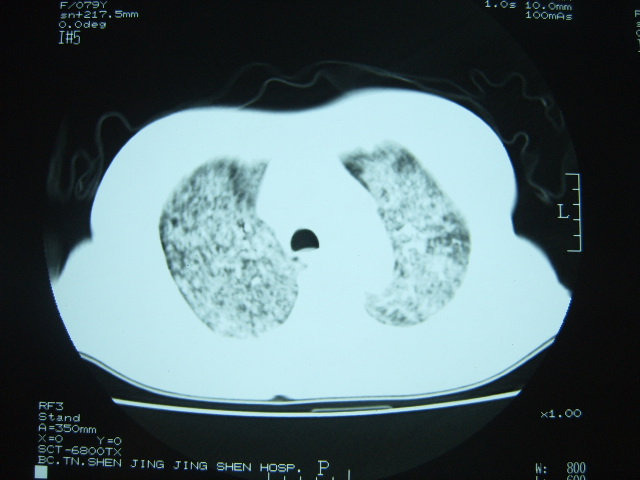

标题: CT7574:双肺病变,请会诊。急!急!

女 79岁,今日高烧,无咳嗽及痰,是否粟粒结核还是?

双肺弥漫小结节状高密度,部分融合,边界不清(因为不是hrct,可能为部分容积效应引起),肺门纵隔内未见肿大淋巴结影。无胸腔积液。

双肺弥漫性结节影,双肺上叶为著.纵隔内可见一肿大淋巴结影,密度较高.支持急性血行播散型肺结核.双侧少量胸腔积液.

双肺弥漫基本均匀分布的小结节状高密度影,部分融合。支持急性血性播散性肺结核。

双肺弥漫性粟粒结节影,双肺上叶为著.密度较高. 两侧少量胸水,心影未见明显增大。临床高热病史,考虑炎症性病变。急性播散性肺结核可能大。肺肾综合征?请结合临床进一步检查。

两肺弥漫分布小结节状高密度影,其大小,密度一致,分布均匀,并可见与后胸壁平行的弧状影

诊断:两肺急性血型播散形肺结核

两肺下叶见高密度钙化灶,支持急性血型播散型肺结核。

两肺弥漫分布之斑点状结节状影,除了血播外,应注意问一下是否有粉尘等病史.但纵隔窗不是很支持.